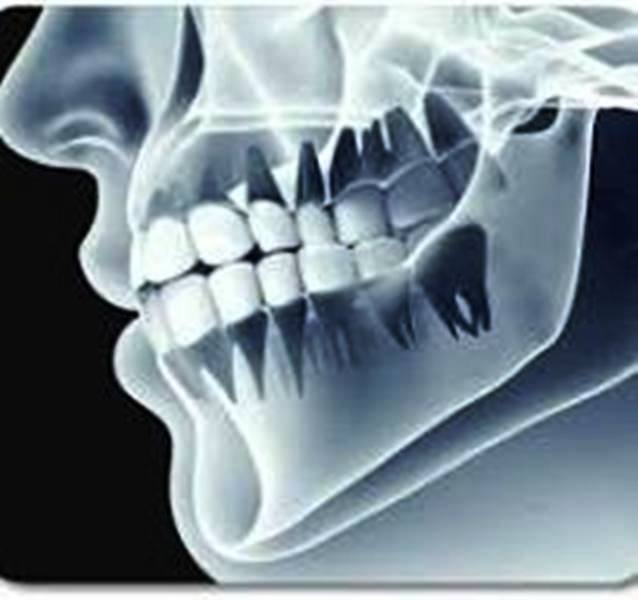

डॉ अल्शिमा बताती हैं कि यदि बच्चा तंदरुस्त है पोषण युक्त भोजन कर रहा है फिजिकल एक्टिविटी भी है तो ऐसी स्थित में हम एक्स रे विधि से जिन बच्चों में 10 से 15 साल के बच्चों में मूंह में एक या दो दांत समय से नहीं निकल रहे हैं तो सबसे पहले बच्चों के मसूड़ों का एक्स रे करके पता लगाया जाता है कि मसूड़ों के नीचे दांत बन रहे हैं या नहीं यदि दांत मसूड़ों के नीचे बन रहे हैं तब वह कुछ समय के बाद निकल आते हैं |